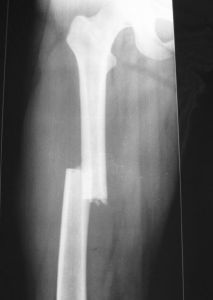

A組:24例採用切開復位DCS內固定。連續硬膜外麻醉,股外側縱切口,切開皮膚及闊筋膜,分離股外側肌,切開骨膜並行骨膜下剝離,充分顯露骨折端。先將髁部骨折復位,使關節面達到解剖復位,用克氏針或持骨鉗將骨折塊固定,再將髁與乾復位,取髁外側股骨長軸線上距遠端關節面2cm為進針點,用95°髁導向器定位,由外向內平行於前髁關節面打入導針,X線證實位置良好,用DCS鋼板模擬測試後,三聯鑽鑽骨,測深、攻紋,擰入動力髁釘、套入鋼板,用持骨鉗將鋼板夾在股骨幹上,分別擰入其它皮質骨螺釘,最後擰緊加壓螺釘尾。有骨缺損者常規植骨。B組19例採用髁鋼板內固定。手術方法基本同前,不同處是:

近年來,隨著手術器材和手術方法的改進,各種新型內固定方法不斷湧現。常用的有逆行髓內釘、95°角鋼板、髁鋼板、動力髁螺釘系統等。

逆行髓內釘適用於股骨遠端斜形、多段骨折、浮膝損傷以及骨質疏鬆者,缺點是進釘和取釘均通過關節操作,對關節有一定損傷 。

DCS具有抗彎、抗扭曲、抗剪力及抗鏇轉作用,能使髁間骨折塊加壓、有良好的力學穩定性,固定可靠、牢固堅強,有利於關節早期活動。DCS為95°釘板結合,符合股骨遠端的解剖結構,適用於股骨髁上、髁間骨折、操作時只需在兩個方向精確安裝,操作簡單、鋼板易於與骨幹軸線一致,便於復位。採用DCS系統固定時內固定物不需要敲擊,只需沿導針滑動,從而保證內植物前進方向。但DCS也有它的局限性,對老年骨質疏鬆症嚴重的應慎用。在動力加壓螺釘和鋼板結合部突出,同時不適用於髁部粉碎性骨折。

綜上所述DCS是治療股骨髁上骨折的手術方法中,固定最穩定、療效較可靠的動力髁固定系統,如能正確掌握適應證,術中準確操作、可以取得良好的治療效果。